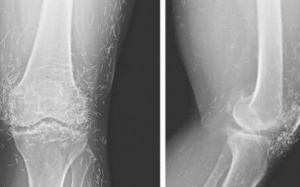

Kiểm tra hình ảnh X-quang đầu gối của một phụ nữ 65 tuổi ở Hàn Quốc, bác sĩ phát hiện hàng trăm chiếc kim châm cứu bằng vàng nhỏ li ti trong mô của bà.